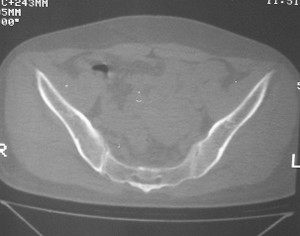

标题: CT7246: F,30岁,下腰痛,同事的片子,请老师们看看,初 [打印本页]

标题: CT7246: F,30岁,下腰痛,同事的片子,请老师们看看,初

典型的致密性髂骨炎

典型的双侧骶髂关节致密性骨炎.

何谓髂骨致密性骨炎?髂骨致密性骨炎是发生于髂骨耳状关节部分的骨质密度增高性疾病。病因迄今不明,可能与妊娠、机械性劳损、病灶性炎症有关。本病好发于20~35岁的育龄妇女,偶见男性。

髂骨致密性骨炎的临床表现与体征:腰骶部疼痛,多呈慢性、间歇性酸痛、隐痛,可向一侧或双侧臀部及大腿后侧扩散,但不沿坐骨神经方向放射,步行、站立、负重及劳累后加重,咳嗽、打喷嚏不能使疼痛明显加重,休息后症状减轻。患者腰骶角加大,局部有压痛和肌紧张,骨盆分离和挤压试验阳性,“4”字试验阳性,化验检查多在正常范围内。x线检查,骶髂关节间隙整齐清晰,靠近骶髂关节面中的髂骨耳状关节部分骨质密度增高,呈均匀浓白边缘清晰的骨质致密带,骨小梁消失,无骨质破坏。本病应注意与早期强直性脊柱炎、骶髂关节结核相鉴别。